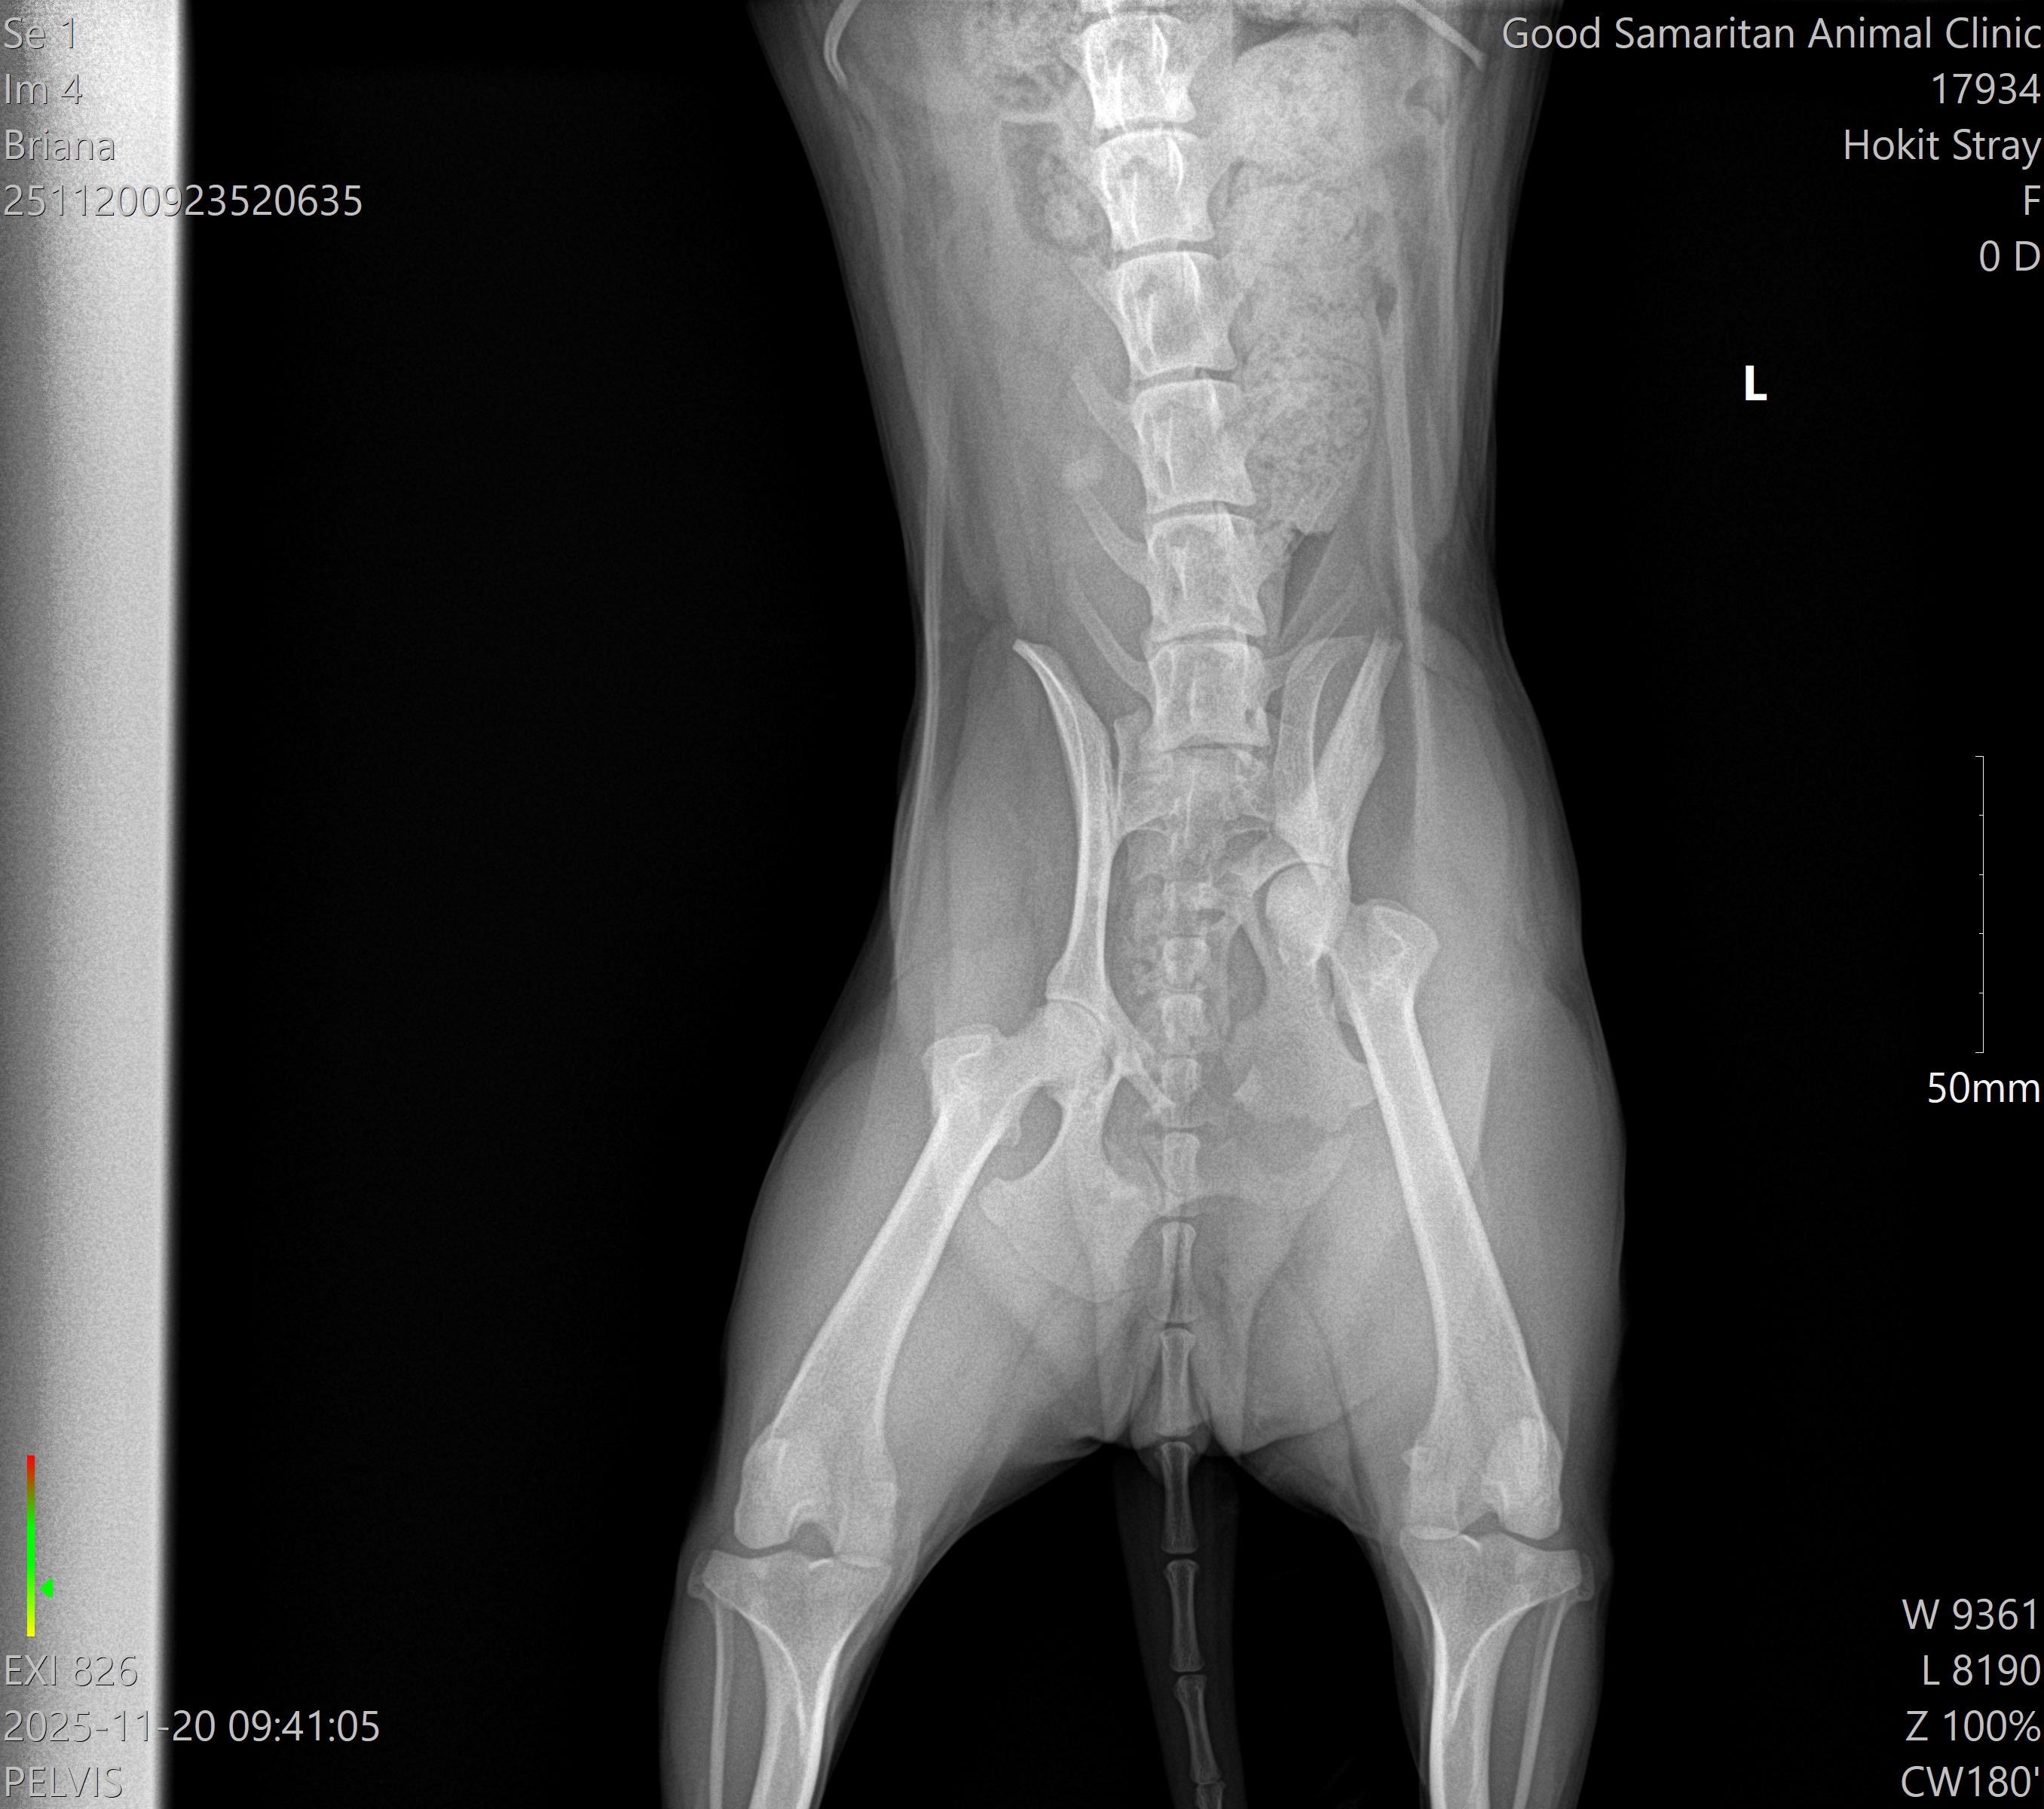

Bunny is a sweet, trusting stray dog who hopped after me on my walk, despite being in obvious pain. I named her Bunny because she followed me home, hopping like a bunny rabbit, and instantly felt a deep connection to her. She was horribly matted and infested with fleas, so I spent hours carefully shaving her and treating her as best I could. The vet estimates she’s only 2-3 years old and believes she was hit by a car, which left her with a serious hip and pelvis injury.

Despite everything she’s been through, Bunny’s gentle spirit shines through. She’s loving, resilient, and deserves a chance at a happy life. Without surgery, Bunny may have to be put down, but with your help, she can get the care she needs to recover. The funds raised will go directly toward her surgery, medication, and physical therapy so she can heal and hopefully find a forever home.